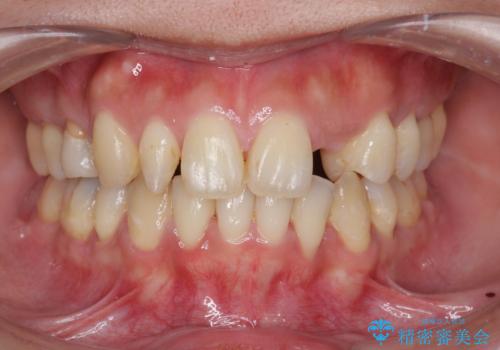

転んで前歯が折れた 色合いの難しい歯のセラミック修復

テトラサイクリン歯といって縞模様の強い歯の色調再現を行いました。

まず保険治療でコンポジットレジン修復を行い、神経の状態を確認した後、クラウンによる修復を行いました。

将来神経が失活する可能性もありますので経過観察する必要があります。